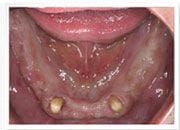

植牙過程

治療前

下顎-植入植體